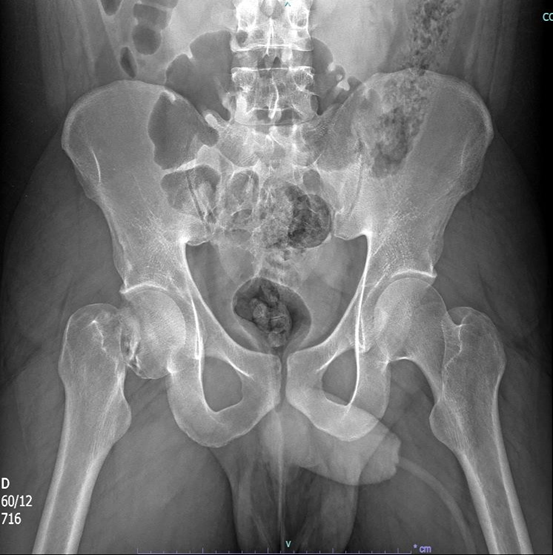

Figura 1: radiografia de tórax.

Frente ao caso, como conduta inicial foram solicitadas radiografias de tórax e pelve no leito, iniciada expansão volêmica com 500 mL de Ringer lactato (apresentando resposta com melhora da PA: 128×71 mmHg e FC 105 bpm), radiografia de fêmur bilateral, joelho bilateral, perna bilateral, braço e antebraço esquerdo, tomografias de crânio, face, coluna cervical, torácica e lombar, tórax, abdome e pelve, sendo as duas últimas com contraste. Além dos exames de imagem, foram solicitados também exames de laboratório.